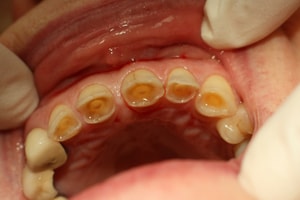

4. Восстановление зубов с высокой степенью износа зубов

Износ зубов - это термин, используемый для описания прогрессирующей потери поверхности зуба из-за действий, отличных от тех, которые вызывают разрушение зубов или травмы зубов.

В большинстве случаев чрезмерный износ зубов вызван шлифованием зубов, но иногда он может быть связан с неправильной техникой зубной щетки.

Независимо от причины, со временем зубы станут маленькими и неприглядными. К сожалению, такие зубы сложны в лечении. Но в некоторых ситуациях можно восстановить эти зубы, построив зубной мост. При этом очень важно восстановить соответствующий прикус; в противном случае у пациента может быть постоянный дискомфорт во время процесса жевания.

Зубная истираемость; зубы становятся маленькими и неприглядными